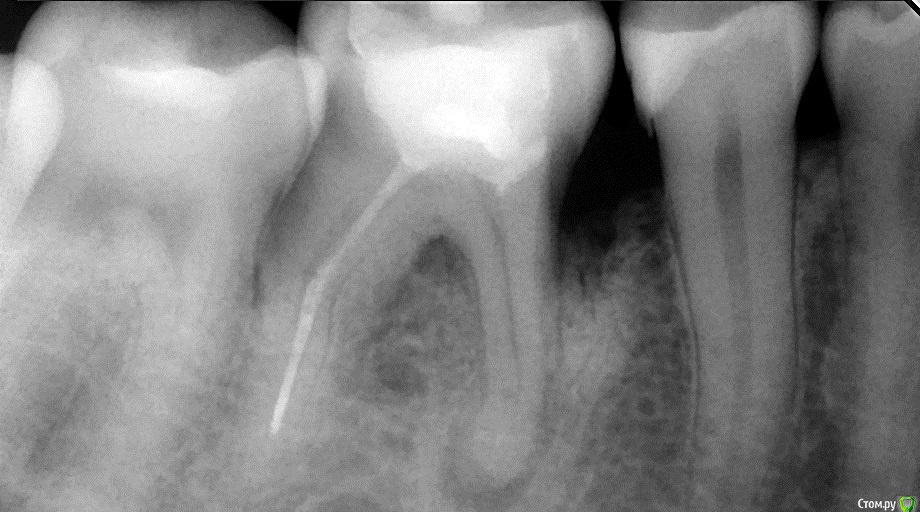

Natalya1984 Опубликовано 11 октября, 2016 Поделиться Опубликовано 11 октября, 2016 Добрый день.В 2007 году был залечен зуб, при удалении нерва 1 канал запломбировали плохо, во втором оставили инструмент, но об этом я узнала совсем недавно. В 2003 на этом же здесне под этим зубом была операция (подсаживали костную ткань). Сегодняшнее состояние зуба на снимке. Можно ли перелечить зуб или оставить как есть, пока сам не выпадет?Заранее спасибо за ответы. Ссылка на комментарий

St. Опубликовано 13 октября, 2016 Поделиться Опубликовано 13 октября, 2016 Здесь ( как минимум мне) не ясна причина кармана в обл.45 46, учитывая относительное благополучие в других участках Ссылка на комментарий

red_butler Опубликовано 14 октября, 2016 Поделиться Опубликовано 14 октября, 2016 Здесь ( как минимум мне) не ясна причина кармана в обл.45 46, учитывая относительное благополучие в других участкахтам вроде нет контактного пункта и пломба на пятерке мягко говоря странная Ссылка на комментарий

DmitrySH Опубликовано 14 октября, 2016 Поделиться Опубликовано 14 октября, 2016 там вроде нет контактного пункта и пломба на пятерке мягко говоря странная это точно, но здесь что-то еще. Может зубочистка + травматический узел. Дистально от 46 тоже кость ушла Ссылка на комментарий